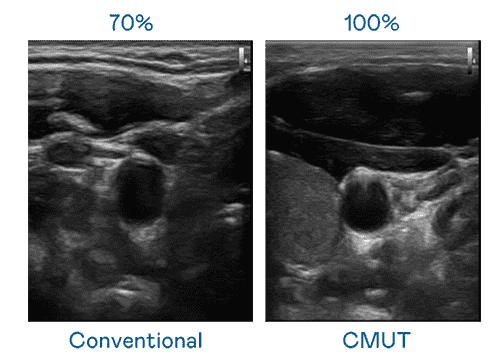

CMUT 技术是一种用电容式微机电元件来产生超音波讯号的技术。。。与传统 PZT 压电式技术相比,,,,CMUT 频宽增加 30%,,,更宽频的超音波讯号让影像解析度大幅提升,,,,是实现高影像品质医疗超音波扫描、、、促进精准医疗发展的关键技术。。

超音波影像的解析度高低,,,首先取决于探头能发出的讯号频宽。。。银河集团 CMUT 可提供高清晰的超音波讯号,,提供高频宽、、、、高灵敏度、、、、影像纹理细节更高的超音波影像,,,,协助医护人员缩短影像判读时间及利用精准的医疗影像进行诊断。。。。